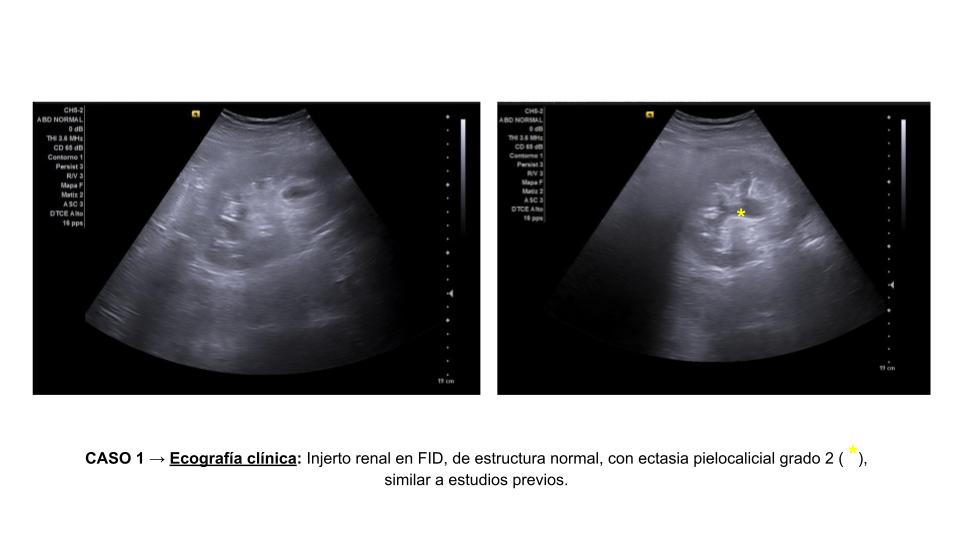

• Caso 1: Riñones nativos con desestructuración, y múltiples quistes. Injerto renal en FID, de estructura normal, con ectasia pielocalicial grado 2, similar a estudios previos.